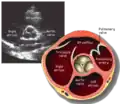

A transthoracic echocardiogram (TTE) is the most common type of echocardiogram, which is a still or moving image of the internal parts of the heart using ultrasound. In this case, the probe (or ultrasonic transducer) is placed on the chest or abdomen of the subject to get various views of the heart. It is used as a non-invasive assessment of the overall health of the heart, including a patient's heart valves and degree of heart muscle contraction (an indicator of the ejection fraction). The images are displayed on a monitor for real-time viewing and then recorded.

A TTE is a clinical tool to evaluate the structure and function of the heart. All four chambers and all four valves can be assessed by TTE, but the quality and visibility of these structures varies from person to person. Other structures visible on TTE include the aorta, the pericardium, pleural effusions, ascites, and inferior vena cava. It can be used to diagnose a heart attack, enlargement/hypertrophy of the heart, infiltration of the heart from an abnormal substance (e.g. amyloidosis). Weakness of the heart, and cardiac tumors. With advanced measurements of the movement of the tissue with time (Tissue Doppler), it can measure diastolic function, fluid status,[1] and ventricular dyssynchrony.